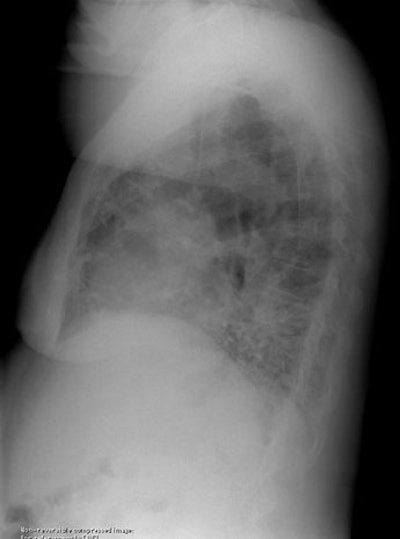

Usual Interstitial Pneumonitis:

The PA and lateral chest radiographs in this patient demonstrate the classic findings in UIP. The lung volumes are diminished. There is a coarsened prominence to the interstitial markings predominantly in a basilar and posterior distribution (noted best on lateral exam), and the heart border has a shaggy appearance (click images to enlarge).